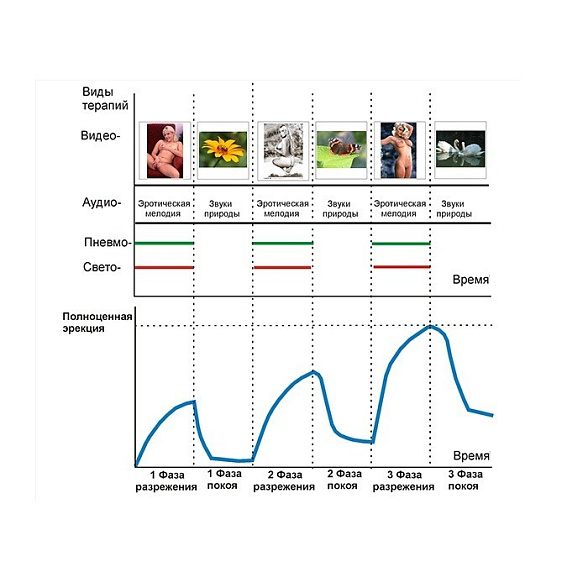

Аппарат "УзорМед-ВАКУУМ-УР"

Этот аппарат представляет собой современное устройство для домашнего применения, объединяющее несколько физиотерапевтических методик. Он предназначен для комплексного подхода к поддержанию мужского здоровья и профилактики ряда состояний.

Основные преимущества устройства:

- Сочетает четыре типа воздействия: инфракрасное излучение, вибрационный массаж, магнитное поле и тепловую стимуляцию.

- Обеспечивает точечное воздействие благодаря специальной ректальной насадке.

- Предлагает широкие возможности настройки с множеством автоматических программ и регулировок интенсивности.

- Имеет два режима работы: упрощенный для самостоятельного использования и профессиональный с набором терапевтических сценариев.

- Изготовлен из качественных материалов с учетом требований к медицинской технике.

Эффективность подобной комбинированной терапии подтверждается клиническими исследованиями, в которых отмечалось значительное улучшение ряда ключевых показателей у пациентов.

Устройство может применяться при различных состояниях, включая хронический простатит в стадии ремиссии, синдром тазовой боли, доброкачественную гиперплазию предстательной железы начальных стадий, а также для реабилитации и в комплексной терапии.

Перед использованием необходимо ознакомиться с полным списком противопоказаний, к которым относятся острые воспалительные процессы, злокачественные новообразования, кровотечения и наличие имплантированных электронных устройств.